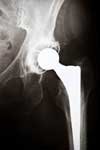

Adverse Events Lead to Hip Recall and Hip Revision Surgery

Upon their development, metal-on-metal hip implants such as the DePuy ASR were first marketed as being more long-lasting, flexible and durable than their metal-plastic/metal-ceramic counterparts. In the early years following their release patients reported complications requiring hip revision surgery and experienced DePuy hip failure. The complaints and resulting studies precipitated the DePuy hip recall in 2010 as the DePuy ASR was withdrawn from the market.

The injuries that necessitate hip revision surgery include premature loosening, instability, difficulty walking, metal poisoning and premature loosening. These symptoms have been exhibited by patients who have been implanted with metal-on-metal systems from other manufacturers.